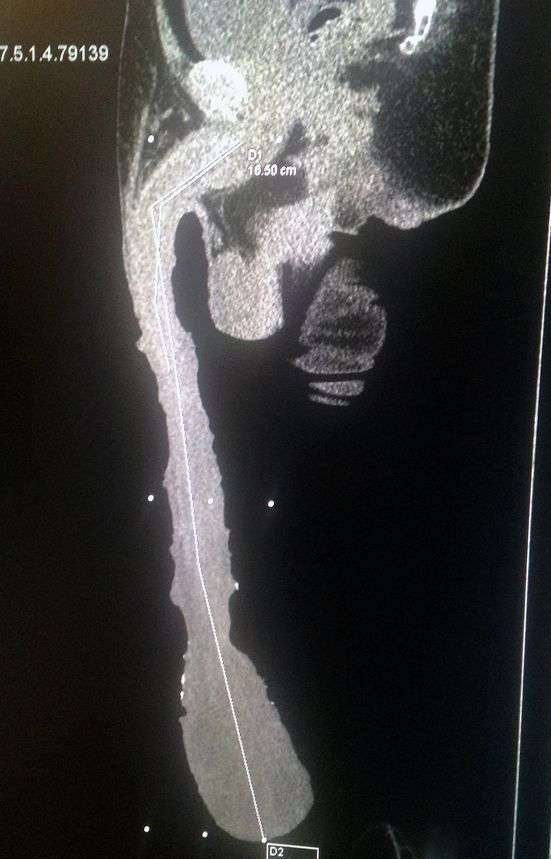

之前我们介绍过54岁墨西哥男子Roberto Esquivel Cabrera,他的GG足足有48cm长。虽然没有被金氏纪录认证,但GG比他还长的男生应该不多。

也许他以后真的能够靠拍A片赚钱,但48cm长的GG真的能够勃起吗?如果不能的话,这条路恐怕也走不通。